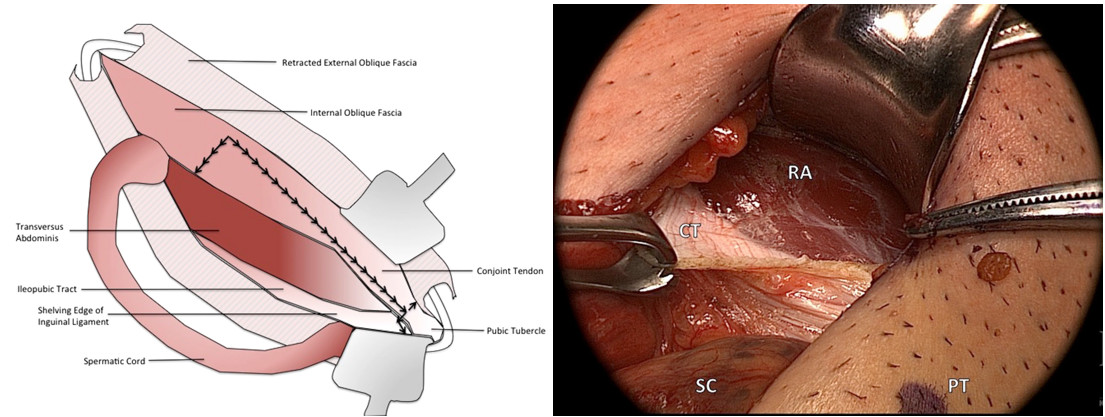

Une incision est ensuite réalisée le long du fascia du tendon conjoint afin d’exposer le muscle rectus abdominis (figure 4). La gaine antérieure du rectus abdominis est libérée de l’os pubien. Une incision au niveau de l’aponévrose du tendon conjoint s’étendant inférieurement et latéralement par rapport au tubercule pubien permet de mettre en évidence ce dernier ainsi que le tendon de l’adductor longus.

Figure 4 : L’incision se réalise le long du tendon conjoint, elle est ensuite étendue supérieurement, inférieurement et latéralement exposant le rectus abdominis (RA).

La ténotomie divise le vecteur de force vertical (aponévrose commune) qui intègre le tendon de l’adductor longus et la gaine du rectus abdominis afin de dissiper les contraintes au niveau de l’os pubien (figure 5).

La ténotomie est réalisée à 1-2cm du tubercule pubien et s’étend inférieurement et médialement, la manœuvre vise à séparer le tendon du muscle adductor longus des fascias le recouvrant.

Figure 5 : Ténotomie de l’adductor longus (AL) et du rectus abdominis (RA).